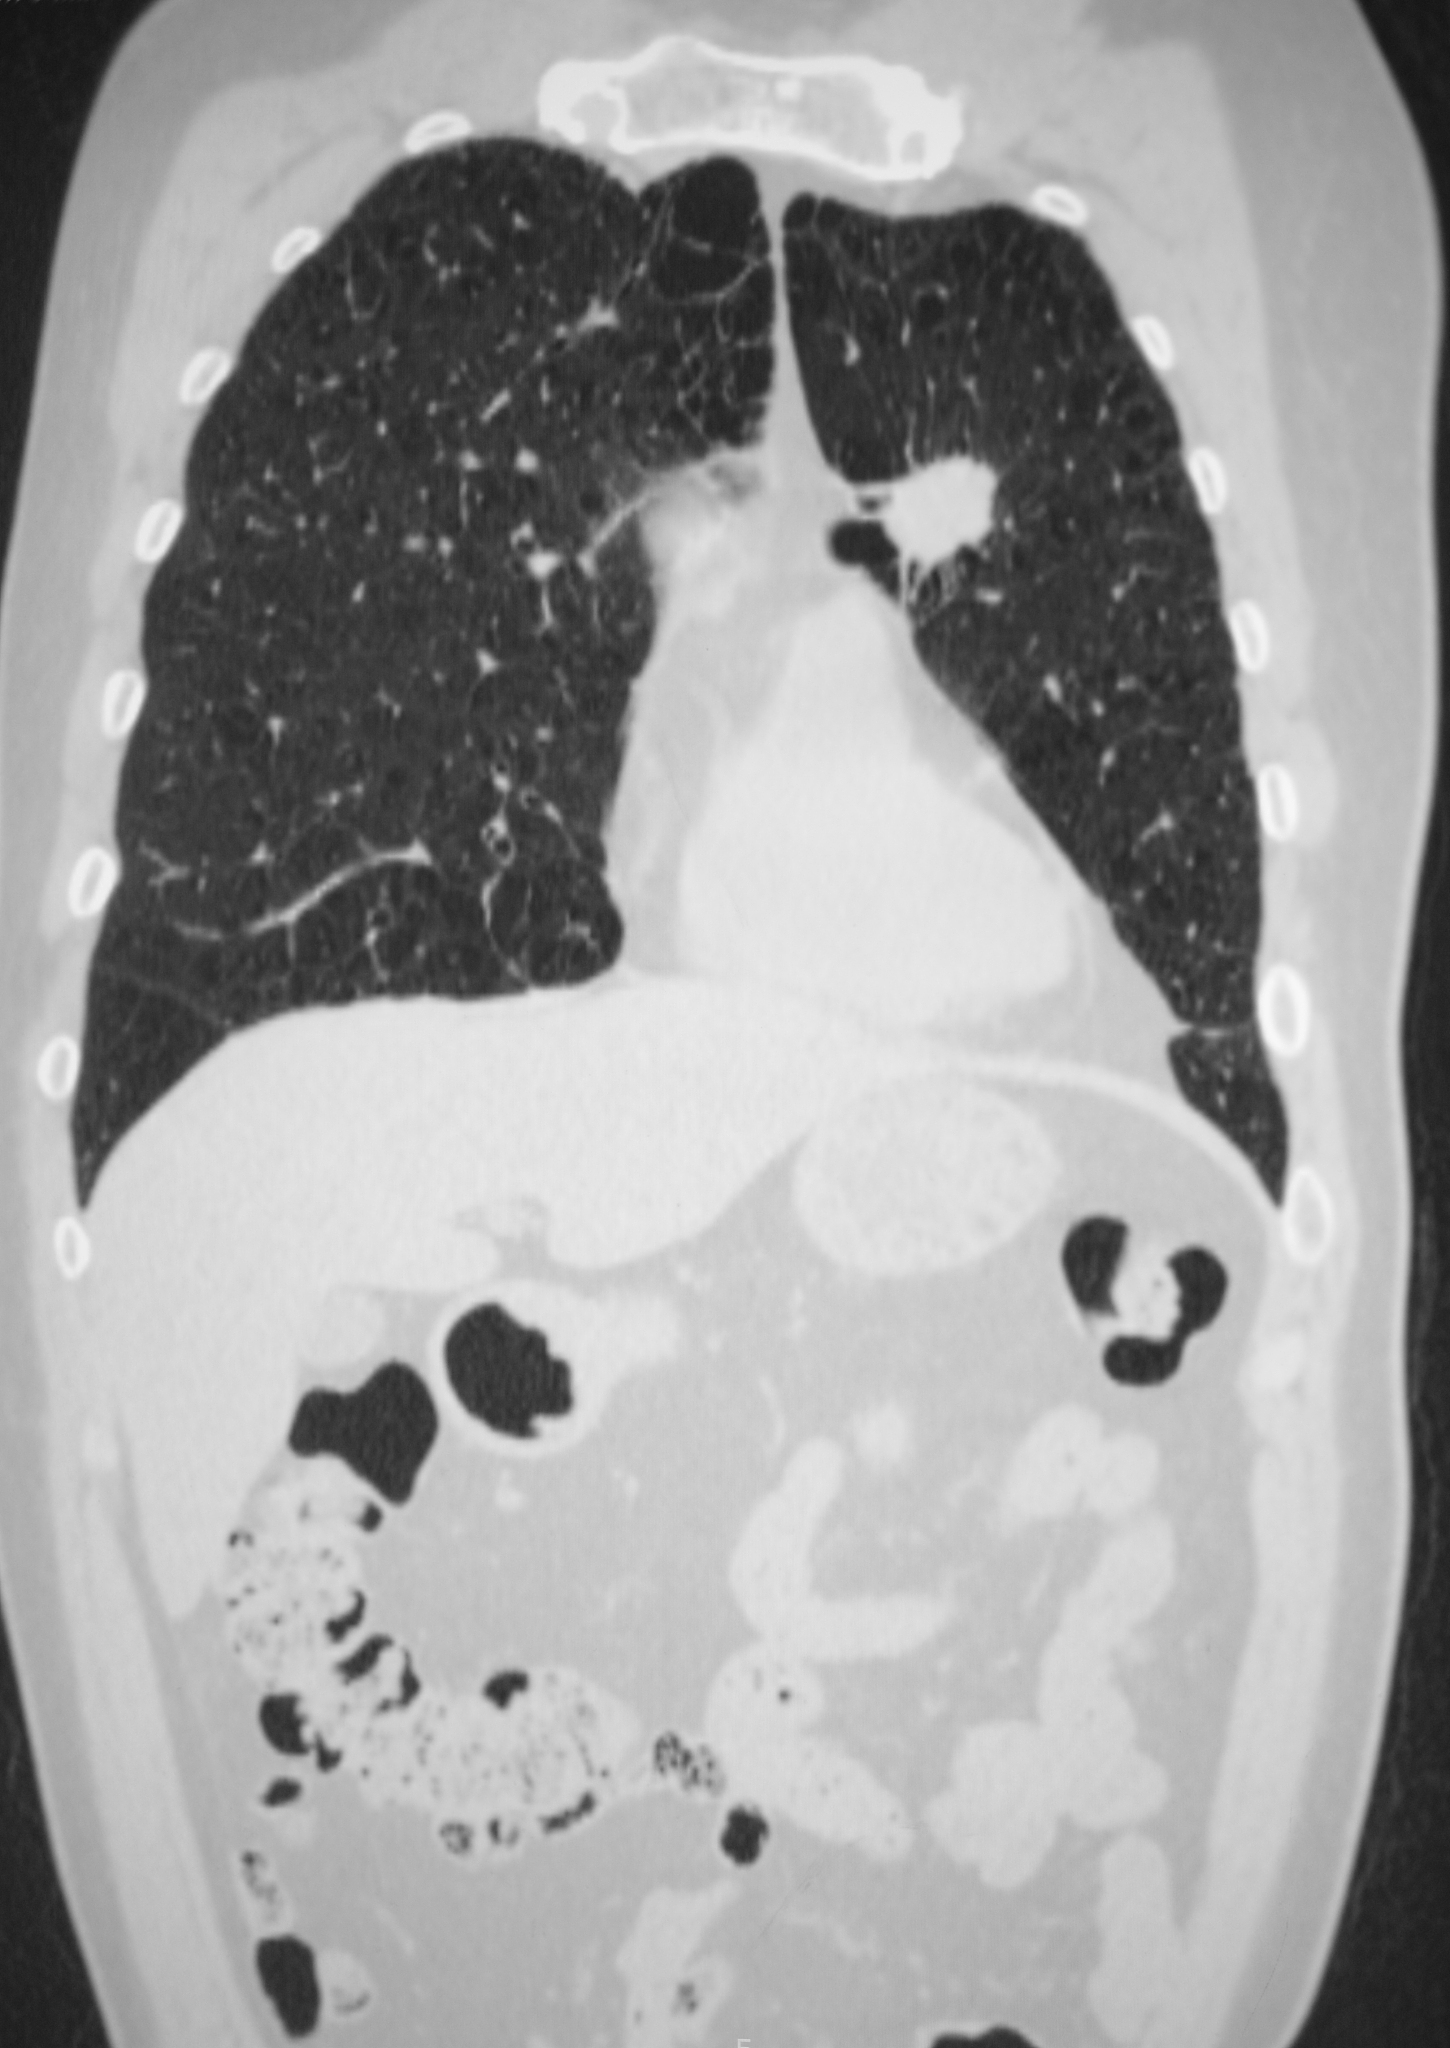

肺癌晚期的影像学表现可以包括以下几个方面:

1. 肺实质改变:晚期肺癌可以导致肺实质受到广泛浸润和破坏,形成肿块或结节。这些病灶通常呈现不规则的形状,并且可能伴有边缘模糊或毛糙。

2. 支气管阻塞:晚期肺癌可能会导致肺部支气管的阻塞。在影像学上,支气管阻塞可表现为远端支气管扩张和积液,形成所谓的阻塞性肺炎。

3. 胸腔积液:晚期肺癌可导致胸腔积液的形成。在影像学上,胸腔积液通常表现为肺野阴影增加或肺实质与胸膜之间的间隙增宽。

4. 淋巴结转移:晚期肺癌常伴有淋巴结转移。在影像学上,淋巴结转移可表现为增大、不规则形状和增强。

5. 肺外转移:晚期肺癌还可以转移到其他部位,如肝脏、骨骼、肾上腺等。在影像学上,肺外转移可表现为相应器官的异常阴影或结节。

需要注意的是,肺癌晚期的影像学表现可以因肿瘤的类型、位置和分期等因素而有所差异,因此具体表现可能会有所不同。最终的诊断还需要结合临床症状和其他检查结果进行综合判断。